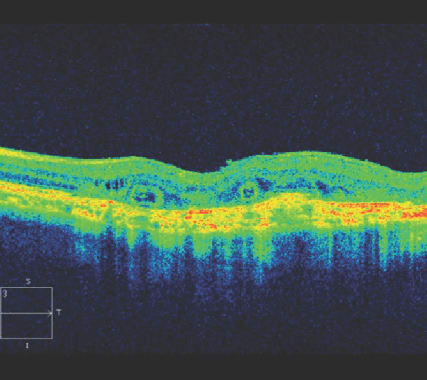

Atypical or chronic central serous retinopathy (CSR) can resemble wet AMD in a 60-year-old patient, but SD-OCT will make the diagnosis apparent (Figure 1). Even in the presence of a pigment epithelial detachment and subretinal fluid, imaging the choroid is key.

A thickened choroid will confirm a diagnosis of CSR and not wet AMD (Figure 1). To image the choroid, one can use enhanced depth imaging or pixel optimization (as with the Cirrus HD-OCT).

Figure 1. A 60-year-old patient was being treated with monthly intravitreal anti-VEGF for wet AMD based on the presence of subretinal fluid. He presented for a second opinion because the fluid was not resolving. As you can see on SD-OCT, the choroidal thickness is greatly increased, indicating the correct diagnosis is central serous retinopathy, not wet AMD. No additional injections were given. If the fluid persists, photodynamic therapy could be considered.